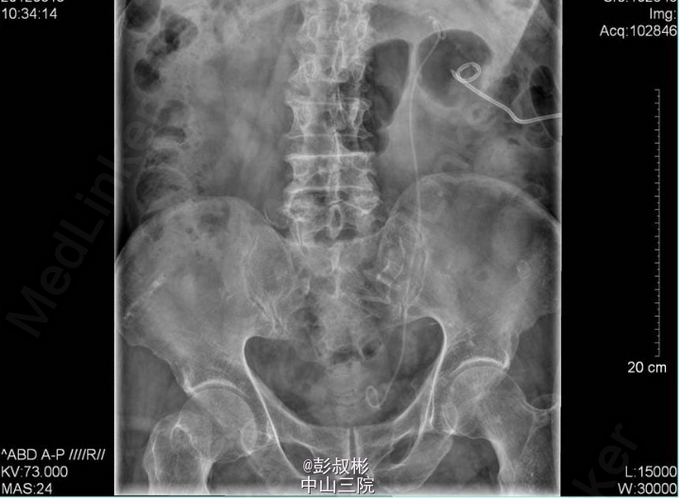

4、入院后处理:完善相关检查,考虑存在泌尿系梗阻引起的肾功能不全,于03-14行“B超引导下经皮肾穿刺造瘘术”, 03-16 复查生化十项:肌酐(酶法)151.000umol/L,尿素氮11.190mmol/L。3-15 3-18 KUB:盆腔左上部见一结节状高密度影,大小约为7mm×7mm。左肾区可见造瘘管影。 3-18于手术室全麻下行“左侧输尿管镜下钬激光碎石术”,术程顺利,术后予抗感染、补液、营养支持等对症治疗。于03-19复查生化十项:尿素氮6.550mmol/L,肌酐(酶法)103.600umol/L。复查KUB提示结石已清除,左肾造瘘管及双J管在位。